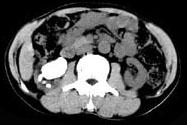

问题 男,53岁,反复右侧腰部隐痛不适2年余,CT如图所示,下列说法正确的是 ( )

选项 A、右肾自截 B、部分肾盏有扩张积液 C、右肾铸型结石 D、右肾钙化 E、右肾多发结石

答案 BCE